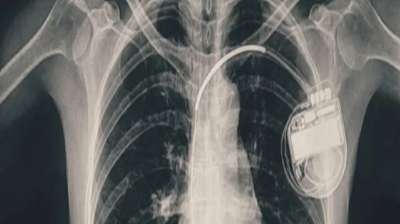

BMHRC के चिकित्सकों की बड़ी सफलता, डुअल चेंबर पेसमेकर से बची बच्ची की जिंदगी

भोपाल। भोपाल मेमोरियल अस्पताल एवं अनुसंधान केंद्र (बीएमएचआरसी) के कार्डियोलॉजी विभाग ने एक दुर्लभ और चुनौतीपूर्ण चिकित्सा उपलब्धि हासिल की है। यहां 13 वर्ष की गैस पीड़ित आश्रित बालिका को...